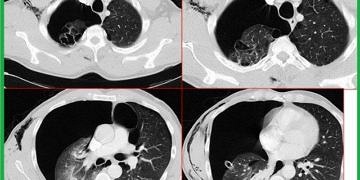

Solunum; ventilasyon, perfüzyon, difüzyondan oluşur. Solunum; dokuların ihtiyacı olan O2‘nin atmosfer havasından alveole, oradan kana ve kandan dokulara ulaşmasını, dokulardan CO2‘nin atmosfer havasına atılmasını sağlar.